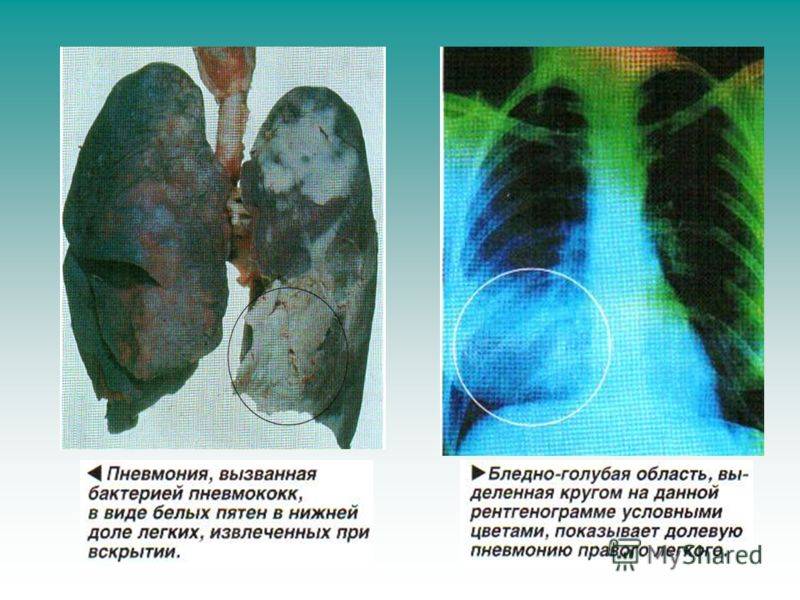

Фотографии, демонстрирующие обнаруженное усиление легочного рисунка

Раздел: Фотодневник открытий